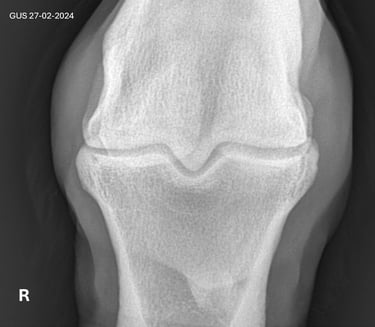

Is uw paard mank, hoefbevangen of is er een vermoeden van een halsprobleem? Dan kan het aangewezen zijn om een radiografisch onderzoek (RX) aan huis uit te voeren. Wij beschikken over een digitaal mobiel radiografietoestel, waardoor opnames eenvoudig bij u ter plaatse kunnen worden gemaakt.

Radiografie (RX)

Consult op de praktijk of aan huis